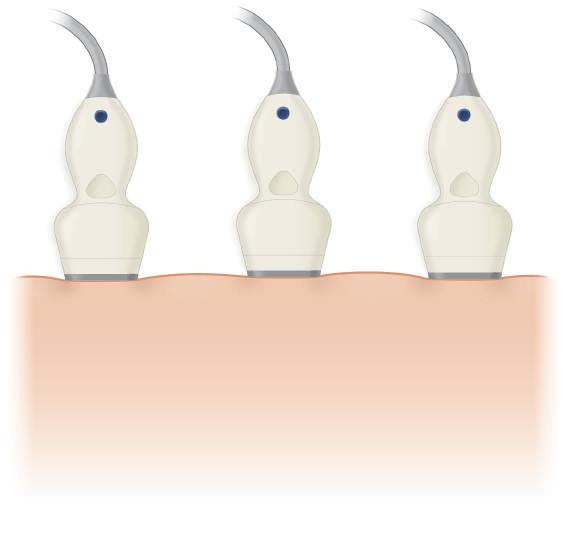

An important source of image degradation and loss of contrast is ultrasound speckle. Speckle results from the constructive and destructive interaction of the acoustic fields generated by the scattering of ultrasound from small tissue reflectors. This interference pattern gives ultrasound images their characteristic grainy appearance (see Fig. 1.6), reducing contrast (Fig. 1.18) and making the identification of subtle features more difficult. By summing images from different scanning angles through spatial compounding (Fig. 1.19), significant improvement in the contrast-to-noise ratio can be achieved (Fig. 1.20). This is because speckle is random, and the generation of an image by compounding will reduce speckle noise because only the signal is reinforced. In addition, spatial compounding may reduce artifacts that result when an ultrasound beam strikes a specular reflector at an angle

FIG. 1.19 Spatial Compounding. (A) Conventional imaging is limited to a fixed angle of incidence of ultrasound scan lines to tissue interfaces, resulting in poor definition of specular reflectors that are not perpendicular to the beam. (B) Spatial compounding combines images obtained by insonating the target from multiple angles. In addition to improving detection of interfaces, compounding reduces speckle noise because only the signal is reinforced; speckle is random and not reinforced. This improves contrast.

greater or less than 90 degrees. In conventional real-time imaging, each scan line used to generate the image strikes the target at a constant, fixed angle. As a result, strong reflectors that are not perpendicular to the ultrasound beam scatter sound in directions that prevent their clear detection and display. This in turn results in poor margin definition and less distinct boundaries for cysts and other masses. Compounding has been found to reduce these artifacts. Limitations of compounding are diminished visibility of shadowing and enhancement; however, these are offset by the ability to evaluate lesions, both with and without compounding, preserving shadowing and enhancement when these features are important to diagnosis.7